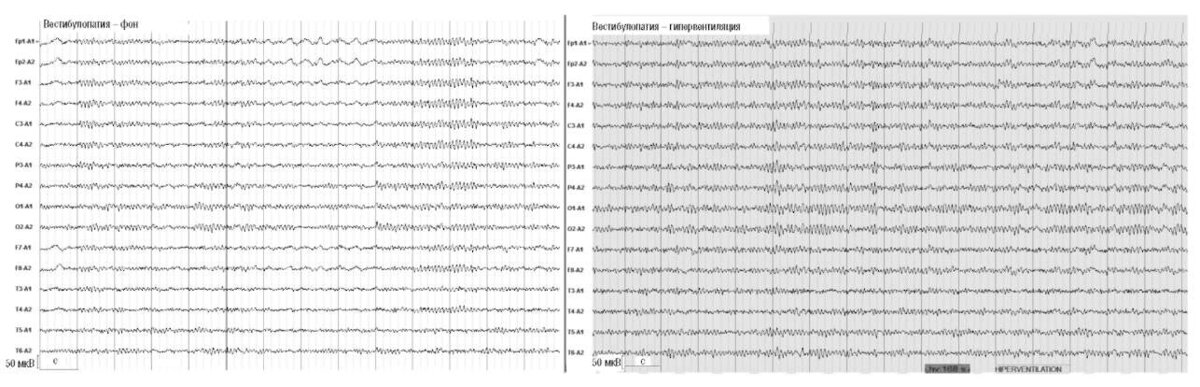

Рис. 2. Женщина, 43 года. Вестибулопатия (повышенная возбудимость вестибулярной системы, склонность к укачиванию и проявлениям морской болезни).Усиление α-активности и ослабление δ-активности на фоне 2-минутной гипервентиляции